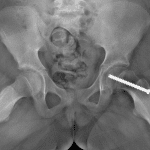

Age: 10

Sex: Female

Indication: Left hip pain

- Posteromedial slippage of the left capital femoral epiphysis, best seen on the frog leg view

- Slipped capital femoral epiphysis (SCFE)

Mildly displaced slipped capital femoral epiphysis (SCFE) on the left. No evidence of SCFE on the right.

No joint malalignment.